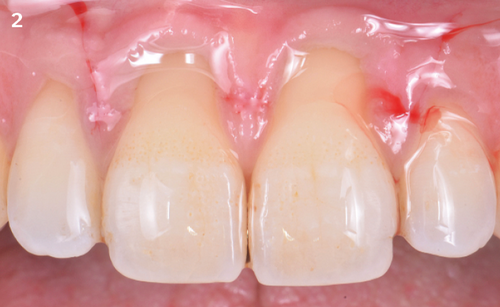

The Situation

A patient (44 years old, male, pipe smoker once a day) with gingival recessions RT-1 on upper central incisors with intact enamel-cement junction. Recession coverage surgery was performed in combination with Geistlich Fibro-Gide®.